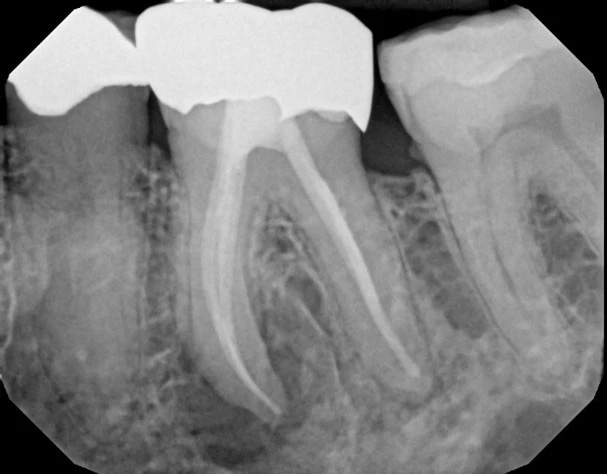

While many may resort to extractions and implants, at Mountain Health Dentistry, we stand confident in preserving natural dentitions. Our expertise lies in performing high-quality, patient-centered, laser-assisted, non-surgical root canal treatments, retreatments, and root-end microsurgeries.

Too often a tooth is extracted that could have been saved from a misdiagnosed vertical root fracture or an “it’s infected” extraction. Maintaining one’s teeth contributes to a better quality of life, better health, and longer life expectancy. We preserve the root to save the tooth, protecting your time and health.